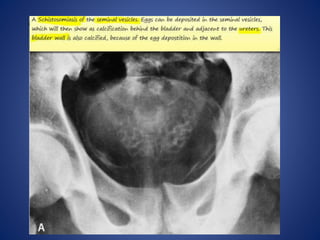

SCHISTOSOMIASIS OF UB

5